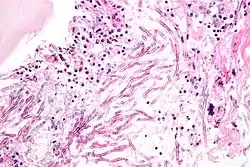

Cryptococcus

Cryptococcus neoformans can cause a severe form of meningitis and meningo-encephalitis in patients with HIV infection and AIDS. The majority of Cryptococcus species live in the soil and do not cause disease in humans. Cryptococcus neoformans is the major human and animal pathogen. Papiliotrema laurentii and Naganishia albida, both formerly referred to Cryptococcus, have been known to occasionally cause moderate-to-severe disease in human patients with compromised immunity. Cryptococcus gattii is endemic to tropical parts of the continent of Africa and Australia and can cause disease in non-immunocompromised people.[1]

Infecting C. neoformans cells are usually phagocytosed by alveolar macrophages in the lung.[11] The invading C. neoformans cells may be killed by the release of oxidative and nitrosative molecules by these macrophages.[12] However some C. neoformans cells may survive within the macrophages.[11] The ability of the pathogen to survive within the macrophages probably determines latency of the disease, dissemination and resistance to antifungal agents. In order to survive in the hostile intracellular environment of the macrophage, one of the responses of C. neoformans is to upregulate genes employed in responses to oxidative stress.[11]

The haploid nuclei of C. neoformans can undergo nuclear fusion (karyogamy) to become diploid. These diploid nuclei may then undergo meiosis, including recombination, resulting in the formation of haploid basidiospores that are able to disperse.[13] Meiosis may facilitate repair of C. neoformans DNA in response to macrophage challenge.[13][14]